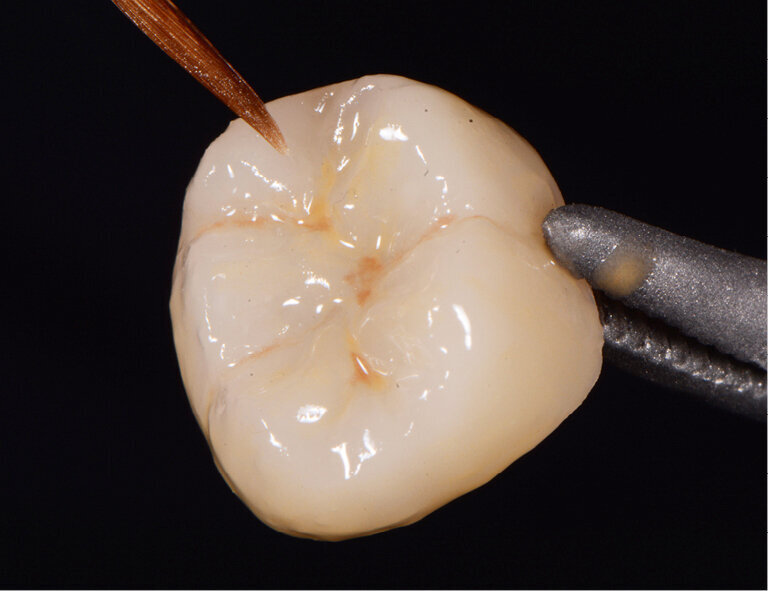

Fig. 4: Characterized and glazed crown

A 45-year-old male patient presented to the practice with a restoration on tooth 46. The tooth had been endodontically treated and was temporized with a filling (Fig. 1). The temporary was removed, the tooth built up with Tetric N-Ceram Bulk Fill and then prepared for the crown restoration (Fig. 2). An impression was taken with a one-step two-phase impression technique using putty and light-body silicone. After scanning the model, the crown was designed in the software suite (inLab, Dentsply Sirona) and milled from an IPS e.max® lithium disilicate block (Fig. 3). After the crystallization firing the crown was stained and glazed (Fig. 4).